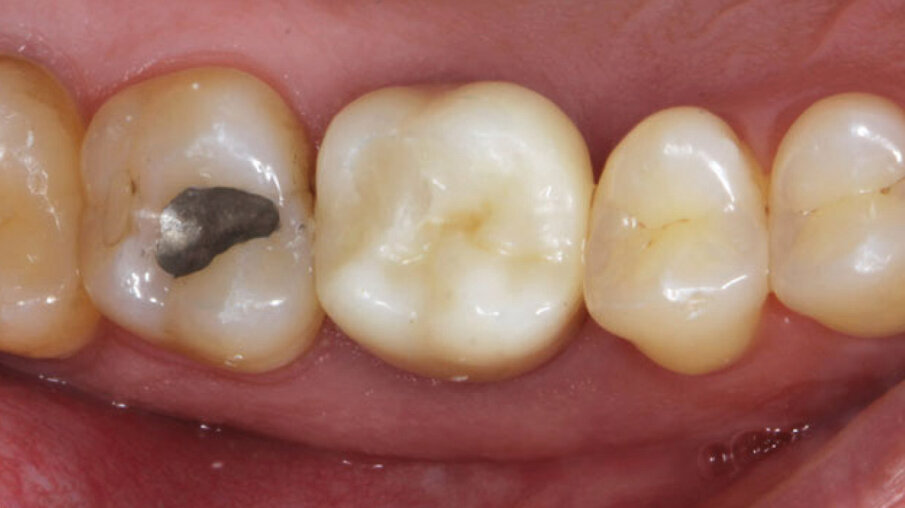

Un paziente maschio (ASA I), senza patologie croniche sistemiche e non fumatore, è stato sottoposto all’estrazione dell’elemento 16 a seguito del fallimento di terapie endodontiche e dell’impossibilità di eseguire un restauro coronale (Figg. 1a, 1b). Nella selezione del paziente sono stati criteri di esclusione: pregressa radioterapia nel distretto testa/collo, assunzione di farmaci che possano indurre ONJ, disordini ematici coagulativi, bruxismo, scarsa igiene orale domiciliare, occlusione instabile, carie non trattate, malattia parodontale non controllata, denti adiacenti a quelli da estrarre con mobilità di grado I o superiore, aspettative di risultato irreali, impossibilità o non propensi a tornare ai controlli di routine e di follow-up. La situazione dei tessuti è stata valutata pre-operatoriamente tramite radiografia periapicala (Fig. 1c) (VistaScan Mini Plus, Dürr Dental). Tramite la CBCT pre-operatoria è stato possibile fare una programmazione implantare. Sulla base dell’anatomia coronale è stata definita la posizione implantare (OnDemand3D, Cybermed), da questa analisi sono stati decisi anche il diametro e la lunghezza dell’impianto.

Fig. 1a_Foto iniziale occlusale.

Fig. 1b_Foto iniziale vestibolare.